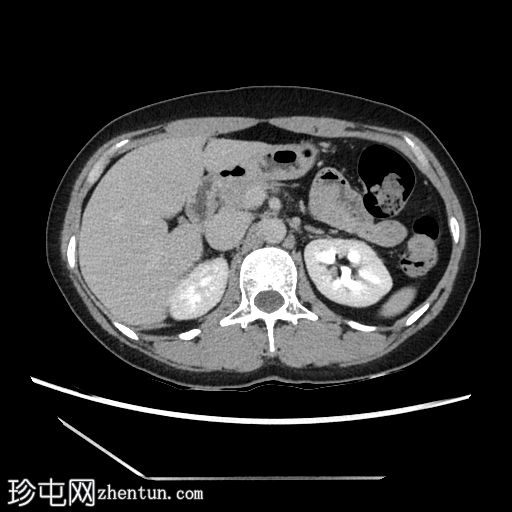

4.jpg

轴向C+期

延迟

在轴向、冠状面和矢状面上均可见肝5/6段病变。动脉期可见周围结节状强化,门静脉期可见进行性向心性充盈,延迟期亦持续存在。这些表现为肝血管瘤的特征性表现。